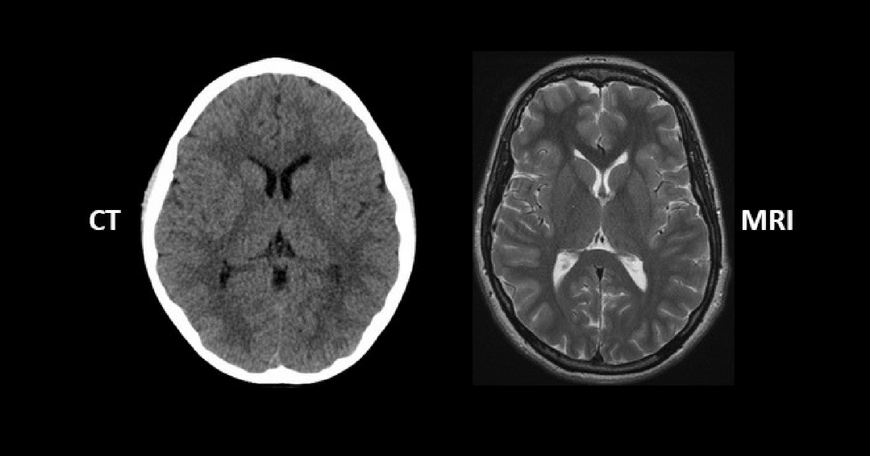

우리 몸속을 들여다볼 수 있다면, 얼마나 좋을까요? 암세포도, 찢어진 인대도, 부러진 뼈도 바로 찾아낼 수 있을 테니까요. 근대 과학이 발전하면서 우리 몸을 자르지 않고도 속을 들여다볼 수 있게 되었습니다. 다양한 기구를 통하여 우리는 우리 몸속을 들여다볼 수 있습니다. 아래는 모두 뇌의 단면 사진인데, 촬영 원리와 특징이 다릅니다. CT와 MRI는 매우 비슷해 보이지만, 작동 원리면에서는 CT와 X-ray가 사촌지간입니다. 우선 X-ray를 알아보고, 이어서 CT, MRI의 작동원리와 어떤 질환의 촬영에 적합한지 알아보겠습니다.

위의 사진에서 처럼 CT 사진에서 뼈 부분은 희게 보이지만, MRI 사진에서 수분이 없는 뼈는 어둡게, 수분이 많은 연한 조직은 밝게 보입니다. 촬영 방법에 따라 T1 영상의 경우 물이 검은색으로 표현됩니다. 실제 CT나 엑스레이처럼 직접 감광지에 기록하는 것이 아니고, 수소원자의 방향을 컴퓨터가 재구성해서 시각화하기 때문에, 이론적으로는 무지개색으로 표현하는 것도 가능합니다.